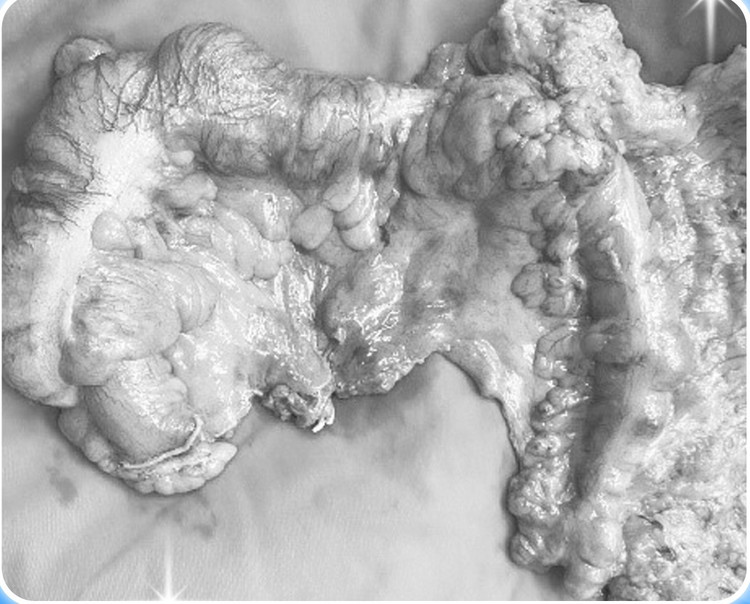

| Khối ung thư được cắt bỏ - Ảnh bVCC |

Điều này cho thấy phương pháp nội soi tiêu hóa đặt sonde qua u giải áp cũng đạt được hiệu quả tương đương với phương pháp phẫu thuật mở hậu môn nhân tạo trên u giải áp, mặc dù người bệnh chỉ cần trải qua một cuộc mổ”.

Sau đó bệnh nhân sẽ được tiến hành hồi sức, bù nước dinh dưỡng để chuẩn bị tốt nhất cho một cuộc mổ cắt khối u. Sau một tuần đặt ống thông giải áp, ekip đã tiến hành mổ nội soi, cắt u và tái lặp lưu thông ruột. Chúng tôi ghi nhận ruột của bệnh nhân giảm phù nề nhiều, việc thực hiện miệng nối cũng dễ dàng, an toàn.